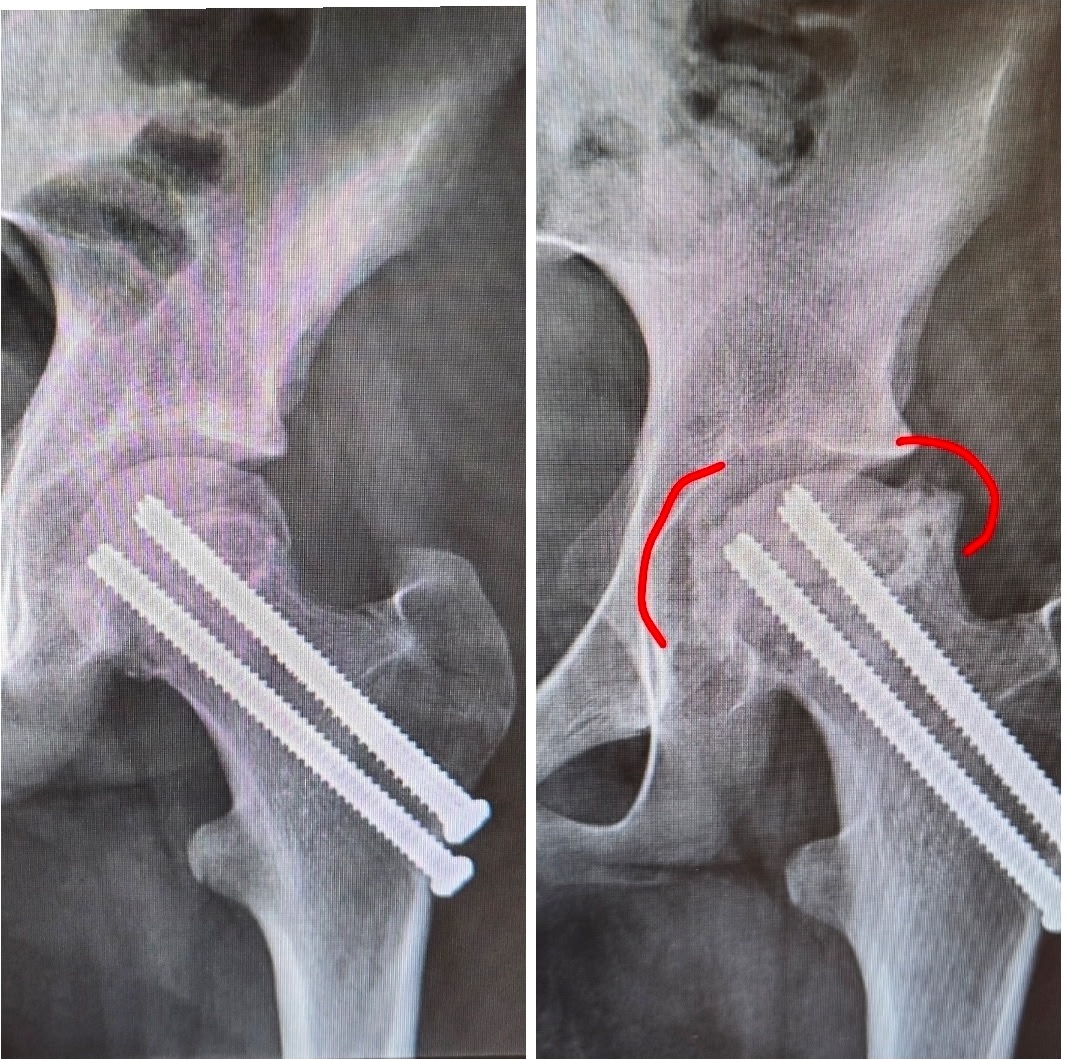

Last year, during a regular gym class, she was hit hard enough to fracture the neck of her hip bone. She underwent surgery where three screws were placed to stabilize the fracture. At first, everything seemed to be healing well , until we got back from moving me into college and we learned that the injury had affected the blood supply to her hip.

Despite everyone’s best efforts, part of the head of her hip bone began to collapse. She had to undergo another surgery in October to remove the screws in hopes of preserving the joint. Unfortunately, even after that procedure, the ball of her hip continued to collapse completely. At this point, a total hip replacement is no longer optional, it’s the only way for her to live without constant pain and regain mobility.